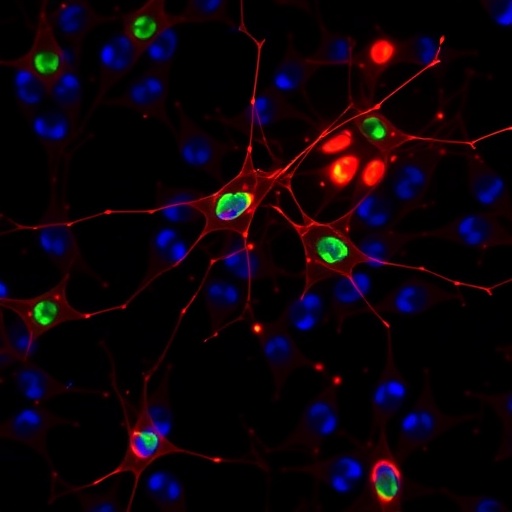

Evaluating Neuroprotective Drugs in Neonatal Rodent Brain Injury

Neonatal brain injury represents a devastating clinical challenge, casting long shadows over developmental trajectories and lifelong neurological function. A groundbreaking...